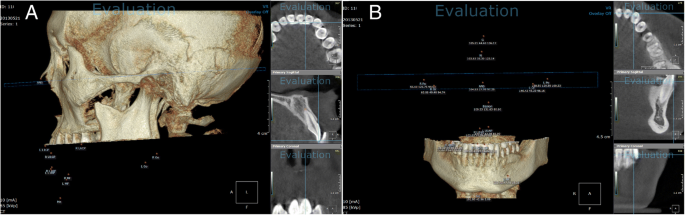

Inclination

To measure tooth inclination, patients were divided into two groups: those who underwent orthognathic surgery and those who did not. In those who underwent orthognathic surgery, the axes of the maxillary teeth were measured in the Frankfort horizontal plane and those of the mandibular teeth were measured in the mandibular plane. In those who never underwent orthognathic surgery, the axes of both the maxillary and the mandibular teeth were measured in the occlusal plane (Fig. 5).

Rotation

To assess the amount of tooth rotation, the angle between the median palatine suture and the extended line of the incisal edge in the maxilla, and the angle between the line connecting both right and left mental foramen and the extended line of the incisal edge in the mandible, was measured. Clockwise tooth rotation was defined as positive (+), while counterclockwise tooth rotation was defined as negative (−). The measured angles before and after orthodontic treatment were analyzed (Fig. 6).